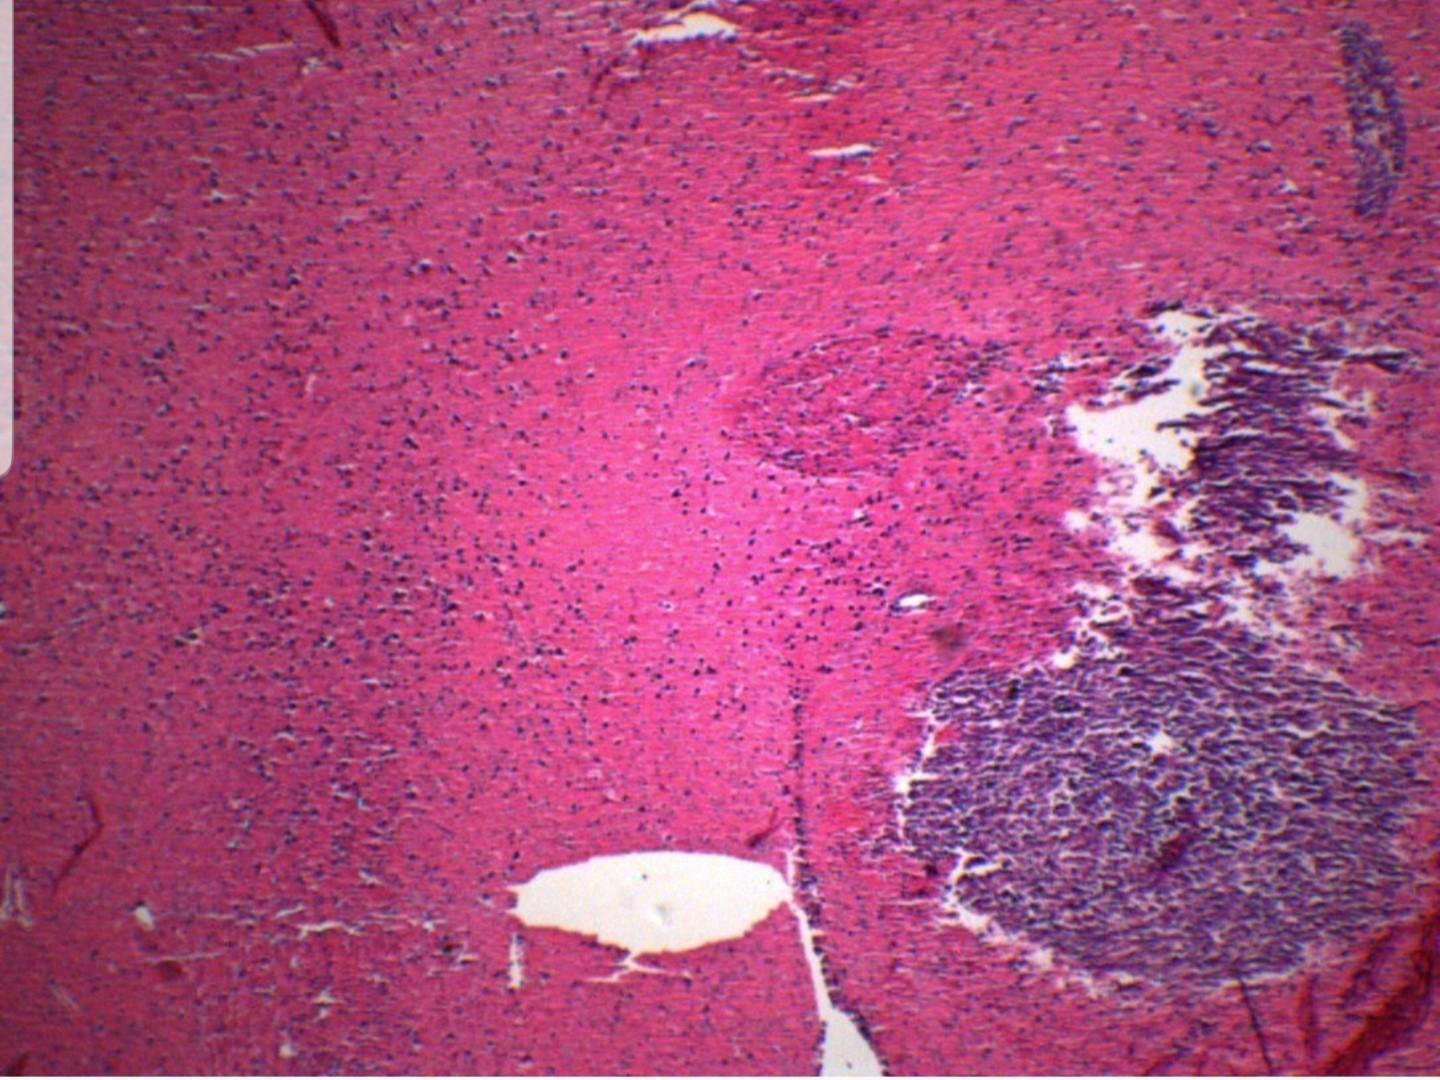

Explain what do human tumours in a mouse background for H&E show.

discuss and identify any differences between the two slides below and the example slide of brain tissue provided below

H&E stain of human tumours in a mouse

Example slide of brain tissue